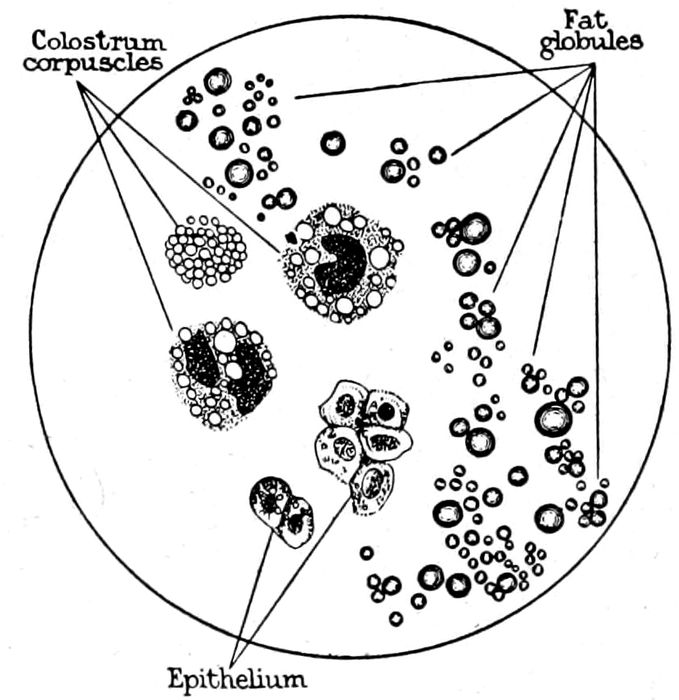

| 130. |

Elements of human milk |

312 |